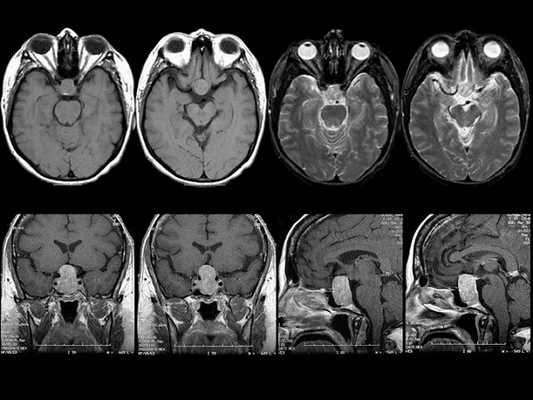

МРТ гипофиза при краниофарингиоме: сканы в разных проекциях

Выявление микроаденомы гипофиза с помощью МРТ: изображения в разных проекциях